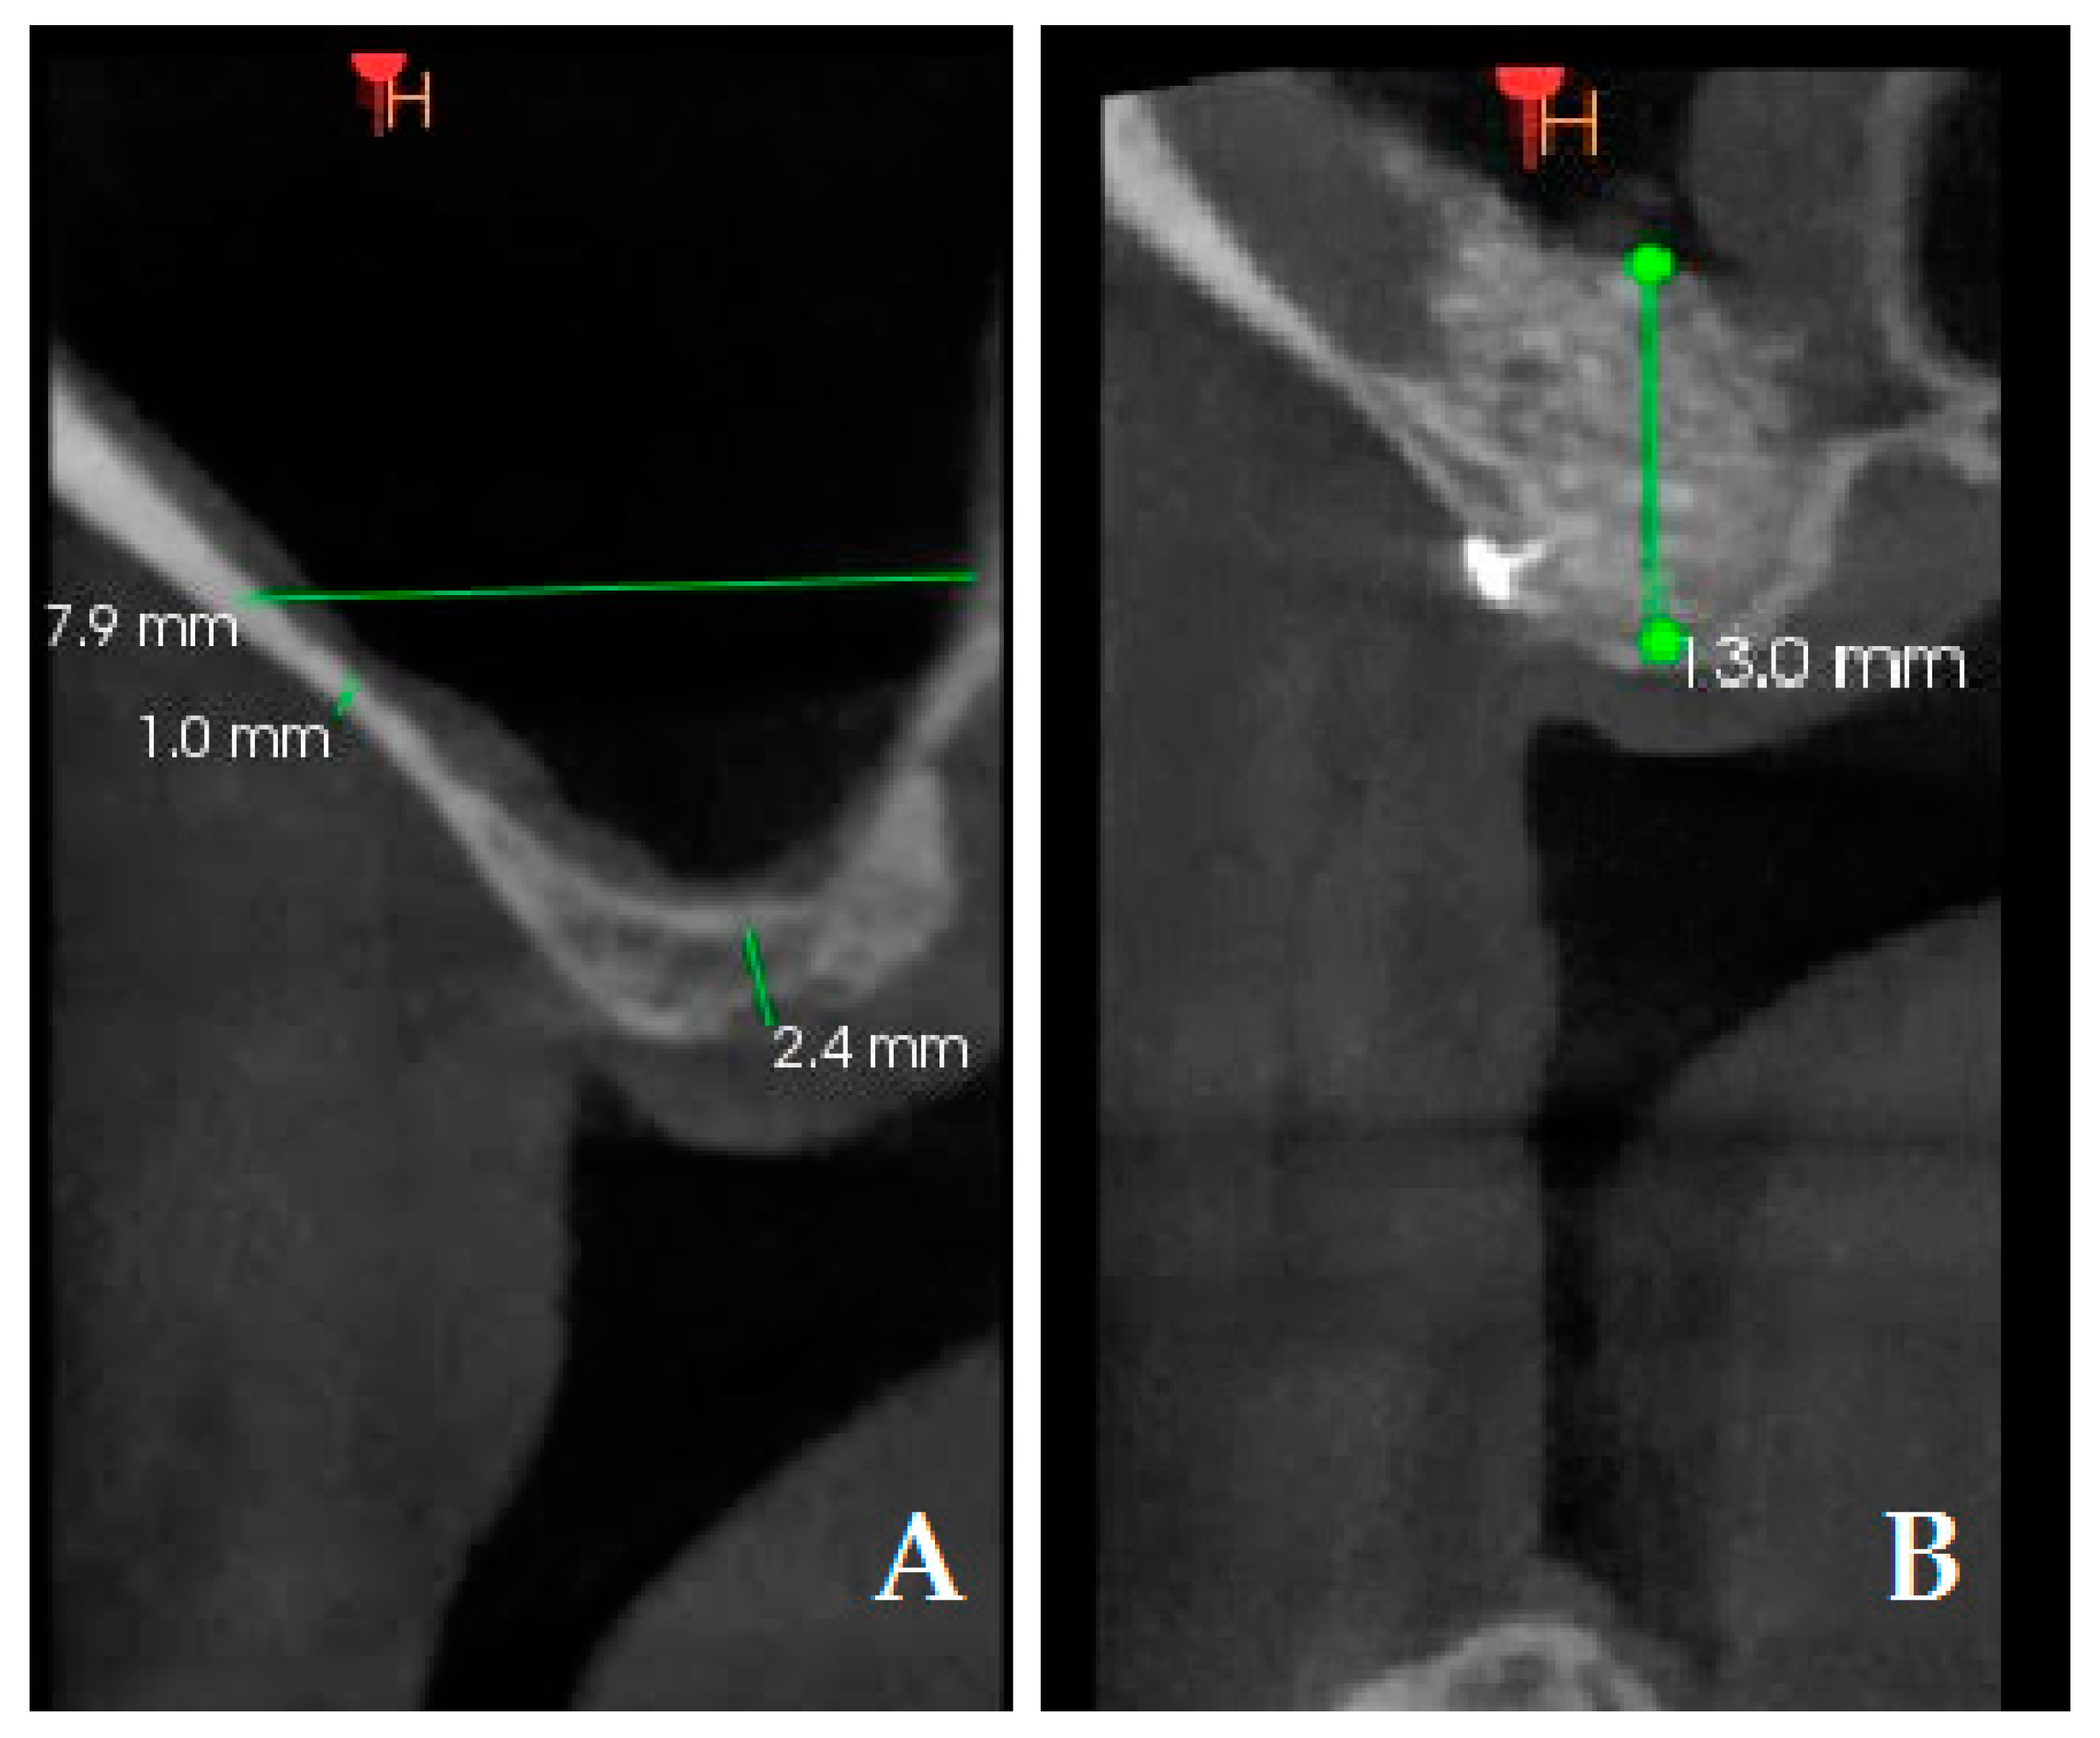

Figure 5.

Cone Beam Computed Tomography (CBCT) measurements: preoperative residual bone (2.4 mm); preoperative thickness of lateral bone in the center (1 mm) (A); postoperative bone height (13 mm). A bone tack is observable in the postoperative CBCT (B).

Another primary objective of this study was to measure the height of the augmented bone between the test group and control group. Measurements were taken on the preoperative CBCT scans and 6-month postoperative CBCT scans (Figure 5). The following radiographic measurements were recorded on the preoperative CBCT in millimeters: (1) preoperative residual bone (PRB); (2) preoperative thickness of lateral bone in the center. Bone height increment (BHI) was recorded on the postoperative CBCT in mm and it was calculated as follows: 6-month bone height value—baseline residual height value.